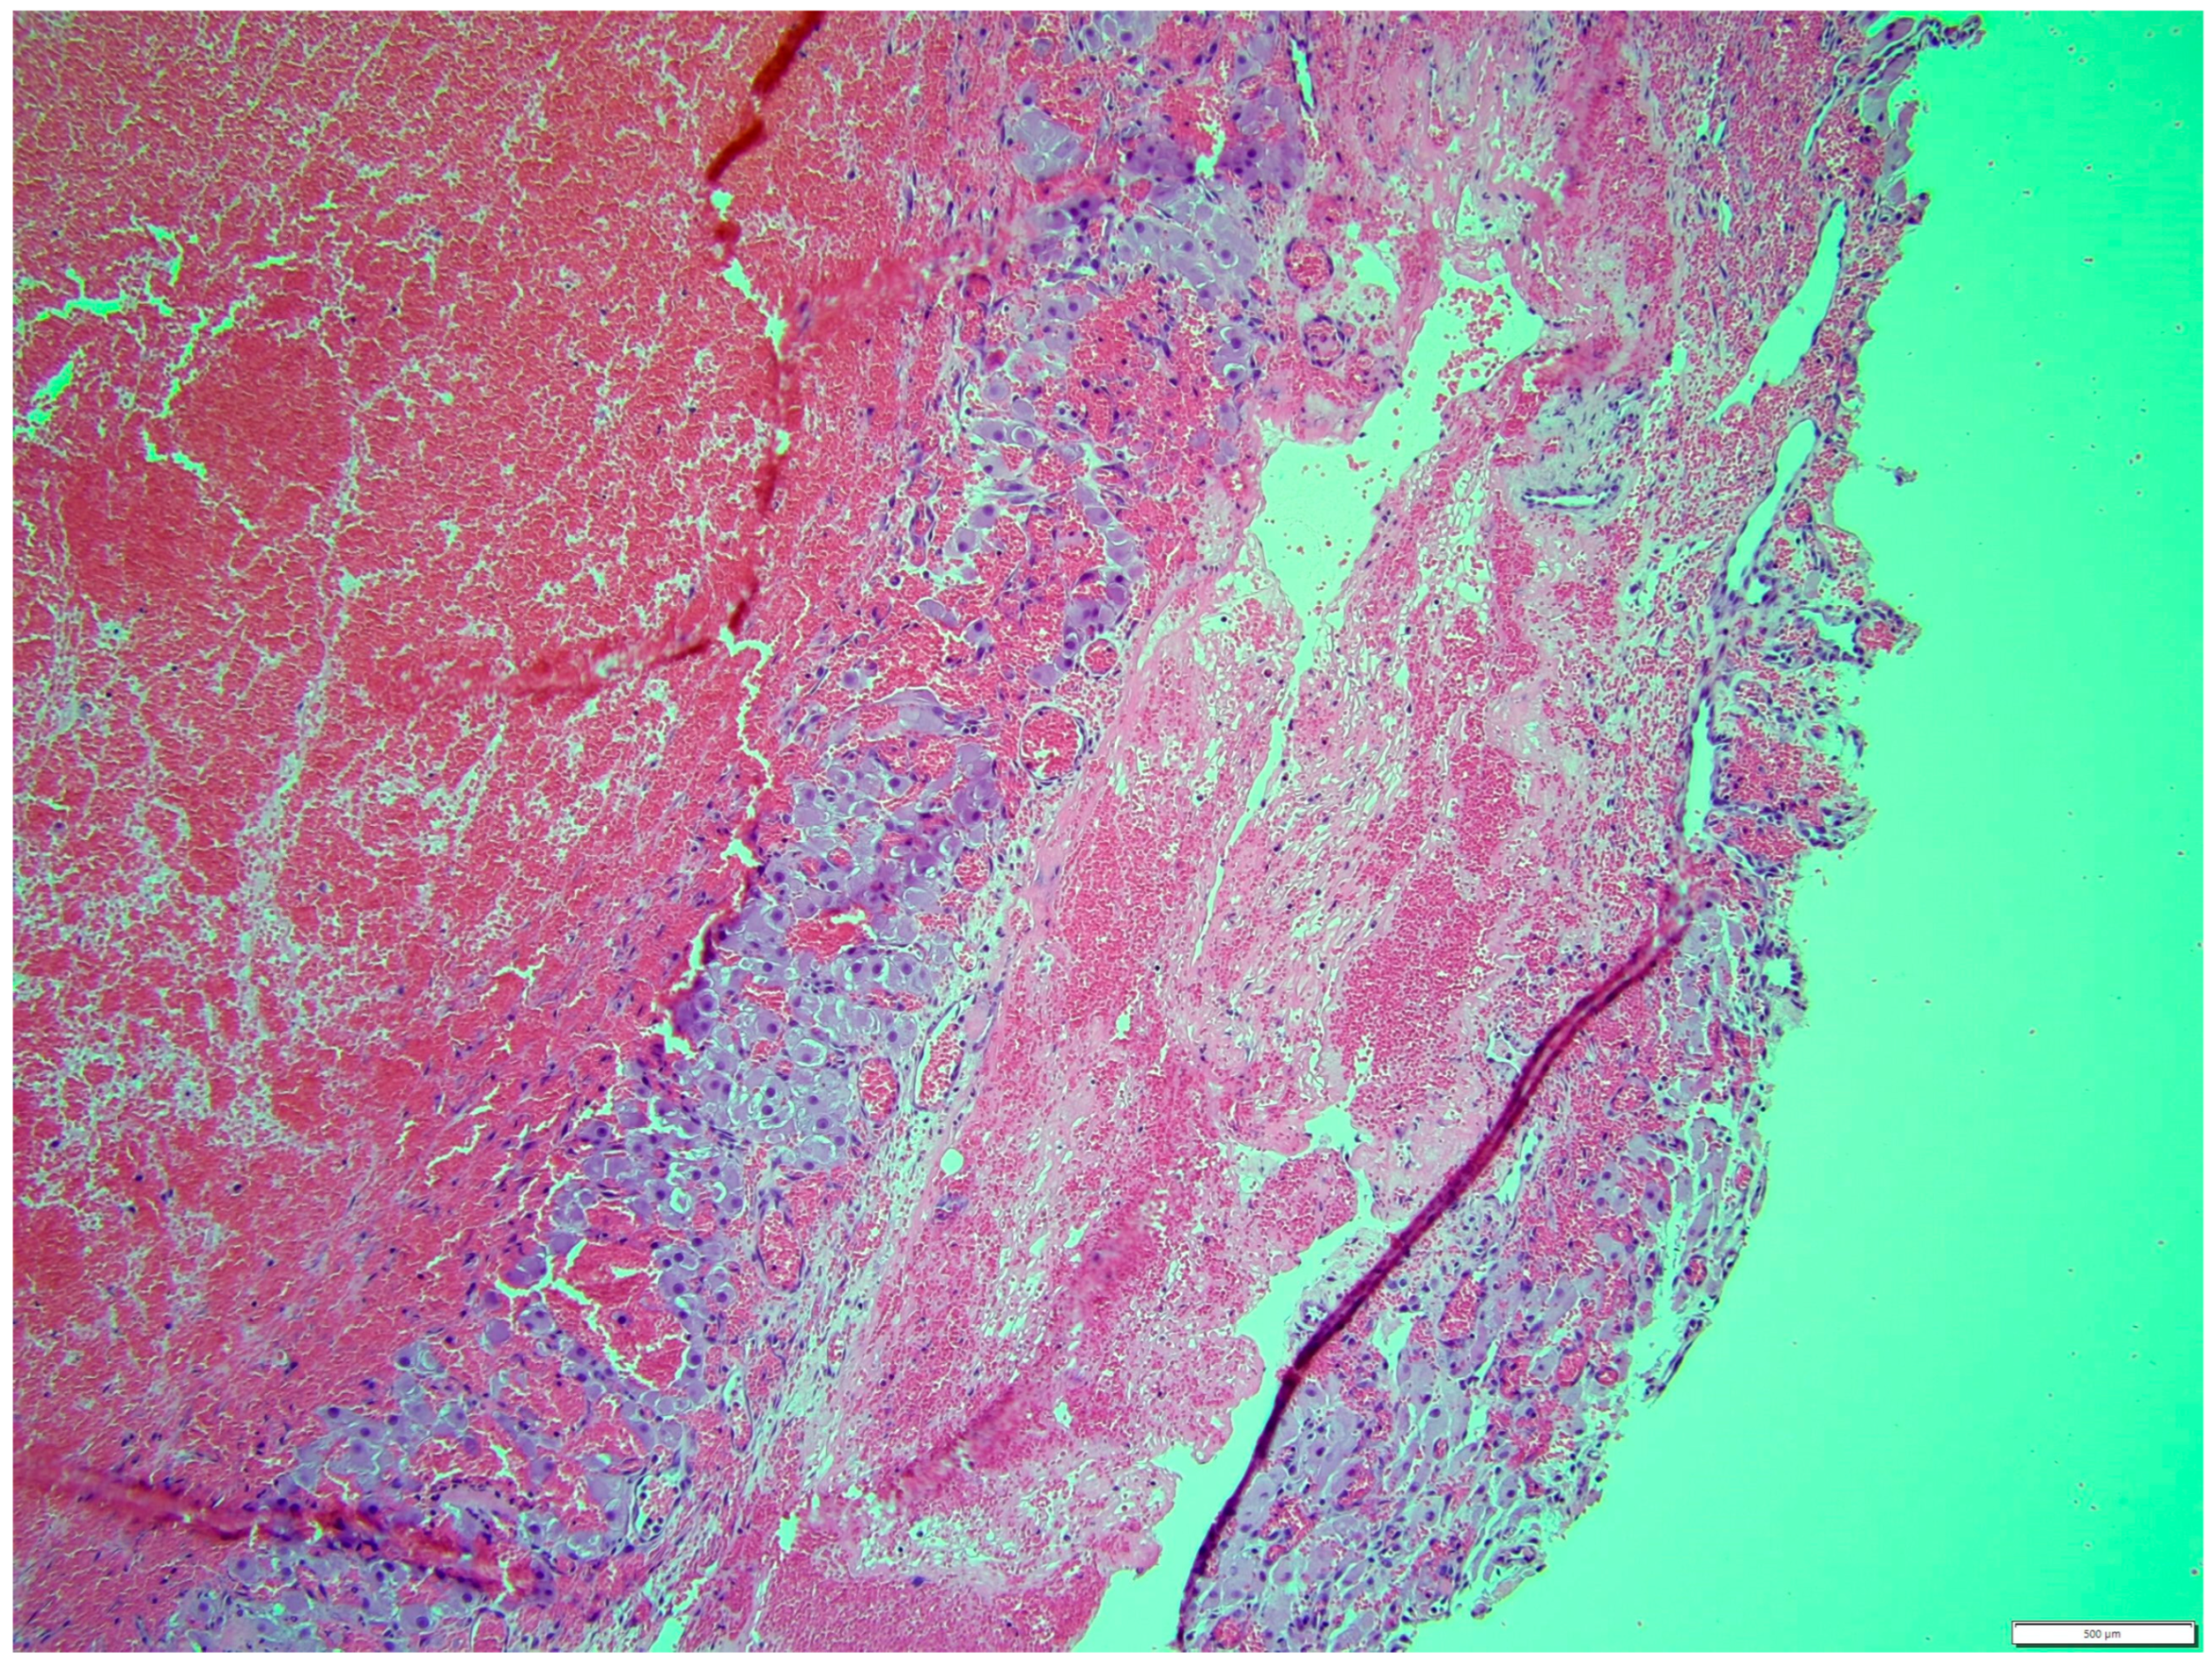

Histologically, both tumor areas were distinctly different from each other (Figure 7 and Figure 8). In the obtained sample for histological examination, the portion of the thecoma was significantly lower (Figure 9). Marked hemorrhage (but not blood-filled lacunae) and very sparse granulation-type connective tissue were observed at the border between both tumor tissues (Figure 10). Hemorrhagic blood masses infiltrated a larger part of the thecoma tissues. A single cystic structure lined with columnar epithelium was found in the hemorrhagic zone, with a very sparse amount of mucus-like material in the lumen (Figure 11).

Figure 7. Distinction between fibroma and thecoma parts. HE, 100× magnification.